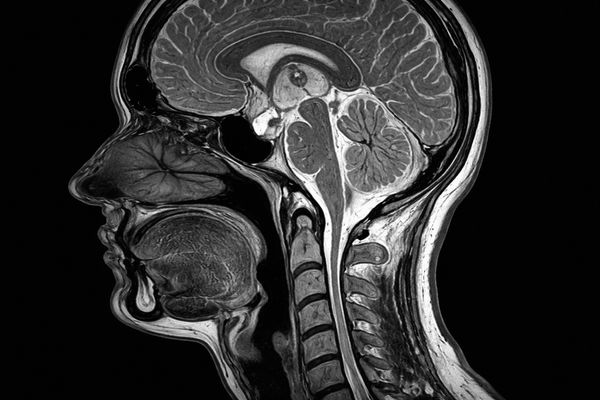

МРТ краниовертебрального перехода применяется для комплексной оценки анатомически сложной зоны, где основание черепа соединяется с верхними сегментами шейного отдела позвоночника. Именно эта область играет основную роль в передаче нервных импульсов и кровоснабжении головного мозга. Поэтому любые изменения могут сопровождаться выраженной неврологической симптоматикой.

МРТ краниовертебрального перехода — это высокоточный метод магнитно-резонансной визуализации, направленный на исследование затылочной кости, атланта, аксиса, верхних отделов спинного мозга, суставных поверхностей, связок и мягких тканей. Технология основана на взаимодействии атомов водорода с магнитным полем, что позволяет получать детальные изображения без использования рентгеновского излучения и с высокой контрастностью структур.